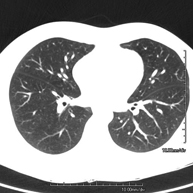

- Tórax- TC Tórax Prueba diagnóstica que consiste en obtener imágenes del tórax de alta definición anatómica (pulmones, corazón, mediastino, grandes vasos, caja torácica, etc.) mediante el empleo de un equipo de TC (Tomografía Computarizada). Dichas imágenes se estudian posteriormente en una estación de trabajo que permite reconstrucciones bidimendionales en diferentes planos del espacio y también reconstrucciones 3D (volumétricas). Algunos estudios requieren el empleo de contraste yodado para mejorar la definición de las imágenes. Prueba diagnóstica que consiste en obtener imágenes del tórax de alta definición anatómica (pulmones, corazón, mediastino, grandes vasos, caja torácica, etc.) mediante el empleo de un equipo de TC (Tomografía Computarizada). Dichas imágenes se estudian posteriormente en una estación de trabajo que permite reconstrucciones bidimendionales en diferentes planos del espacio y también reconstrucciones 3D (volumétricas). Algunos estudios requieren el empleo de contraste yodado para mejorar la definición de las imágenes.

- TC Tórax alta resolución Prueba diagnóstica que consiste en el estudio del pulmón mediante el empleo de un equipo de TC (Tomografía Computarizada) obteniendo imágenes bi y tridimensionales que permiten un estudio anatómico altamente específico del pulmón, pudiendo valorar estructuras anatómicas de tamaño muy pequeño. Es una técnica muy importante en el estudio de los pacientes con sospecha de enfermedad pulmonar. Prueba diagnóstica que consiste en el estudio del pulmón mediante el empleo de un equipo de TC (Tomografía Computarizada) obteniendo imágenes bi y tridimensionales que permiten un estudio anatómico altamente específico del pulmón, pudiendo valorar estructuras anatómicas de tamaño muy pequeño. Es una técnica muy importante en el estudio de los pacientes con sospecha de enfermedad pulmonar.